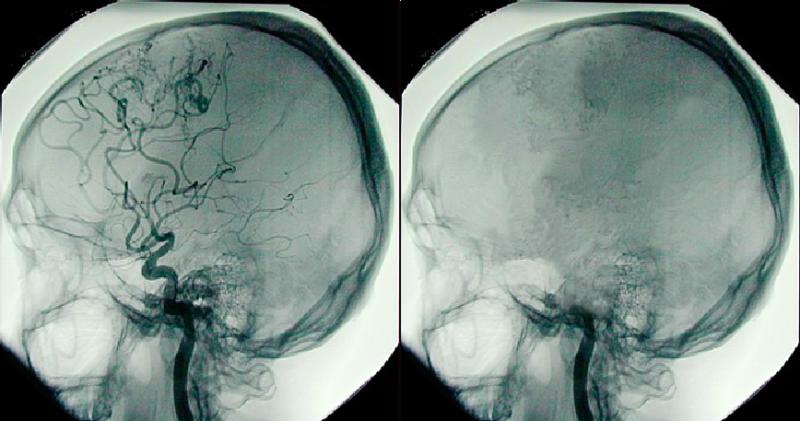

Beyin cerrahisi, merkezi sinir sisteminin hastalıklarını, yaralanmalarını ve bozukluklarını tedavi etmek amacıyla uygulanan cerrahi bir dalıdır. Bu alan, beyin, omurilik ve sinir sisteminin çeşitli yapıları üzerinde gerçekleştirilen cerrahi işlemleri içerir. Beyin cerrahisi, hem acil durumlarda hem de planlı cerrahilerde önemli bir rol oynamaktadır. Beyin Cerrahisinin Tarihçesi Beyin cerrahisinin kökleri, antik çağlara kadar uzanmaktadır. İlk cerrahi müdahale örneklerine Mısır, Yunan ve Roma dönemlerinde rastlanmaktadır. Ancak, modern beyin cerrahisi, 19. yüzyılda anestezi ve asepsi tekniklerinin gelişimiyle mümkün hale gelmiştir. Bu dönemde, birçok cerrah, beyin ameliyatlarının güvenliğini artırmak amacıyla çeşitli teknikler geliştirmiştir. Beyin Cerrahisinin Alanları Beyin cerrahisi, birkaç farklı alt dalı içerir. Bunlar arasında: